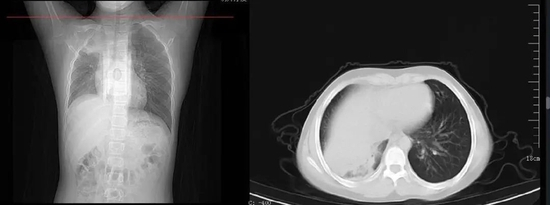

胸片上患儿的一侧肺部组织大面积变白

已经成了大叶性肺炎

男孩的影像学检查结果

“白肺是一种俗称,是重症肺炎的影像表现。”是指重症大面积肺炎后出现透光度下降的影像学表现。”福建省立医院北院(省老年医院)急诊科副主任、呼吸与危重症医学科副主任医师郭永明介绍,受病毒、细菌感染侵袭,肺部出现炎症,从而导致肺组织渗出增加、肺的通气功能、弥散功能降低。这时候做CT或者拍x线片,在影像下就表现为“双肺野大面积的白色的毛玻璃影”。